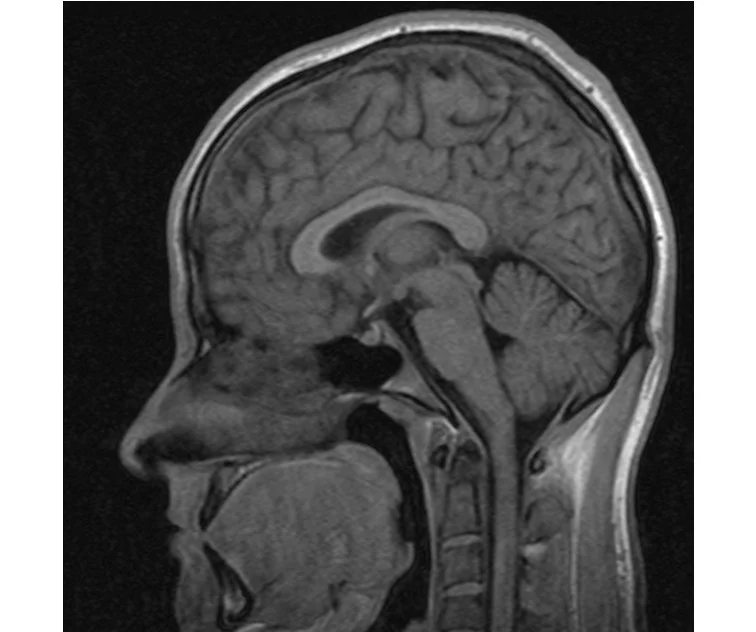

глянте на снимки томографии плиз

делал в обласной на siemense.В заключении выданом мне через 15мин.после мрт (легкая дегидрация)

Меня смутил факт выдачи заключения через 10мин(наверно они у них зарание напечатаные)я не медик.достаточно мимолётного взгляда на снимки?А вы видете на них гидроцефалию? Я лиш спросил куда идти с результатами томографии?и не хотел никого роздражать.

Я попросил взглянуть на снимки и сказать видна.ли на них гидроцефалия?или куда обратится за консультацией по этому вопросу?В мрт снимках наверно розбирается любой нервопатолог(я так предположил)

Я уже говорил, что независимо от того, есть на МРТ гидроцефалия или нет, лечиться тебе нужно только в том случае, если есть какие-либо проявления болезни, иначе на все эти анализы можешь забить... Но давай все-таки разберемся с томограммой.

Итак, с самого начала томограмма обозначала срез какого-либо органа на определенной глубине, позволяла заглянуть вовнутрь. При компьютерной томографии аппарат делает десятки срезов головного мозга в разных направлениях и из этого множества срезов он моделирует полноценное объемное изображение мозга в натуральную величину. Обрати внимание, компьютер работает не с этими миниатюрными изображениями, а с трехмерной моделью в масштабе 1:1. Эту модель вдоль и поперек анализирует суперсовременный компьютер, выполняющий миллионы операций в секунду. Только ***** может пытаться перепроверить компьютер, ведь человеку не хватит всей жизни чтобы проанализировать то, что компьютер с тобой сделал за 10 минут. Я хочу, чтобы ты это понял!

Ты разместл здесь несколько миниатюр и хочешь, чтобы врач по ним создал полноценное объемное изображение в натуральную величину, а потом осмотрел его со всех сторон и дал заключение? Но ведь это невозможно. Это просто насмешка над врачом, это издевательство над здравым смыслом. Принеси Букеру уменьшенный в 50 раз снимок зуба и спроси у него, в каком состоянии там корневые каналы. Или давай я дам тебе скрин со спутниковой карты города и попрошу тебя описать, какого цвета и какой модели запечатленная со спутника машина, какой у нее гос.номер, сколько в ней пассажиров, сколько из них мужчин и сколько женщин...